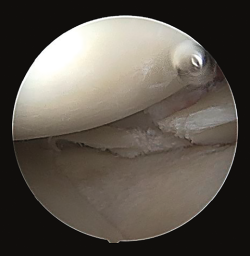

The plain radiographs revealed bone avulsions of the posterior part of the tibia (Figure 1).

Figure 1. Lateral radiographic view of the knee, showing bone involvement in the posterior part of the tibia.